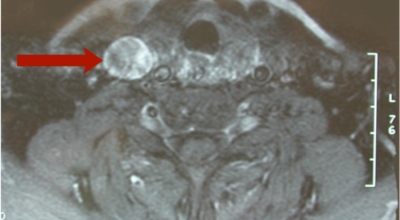

턱 아래,목 부위 앞쪽에 존재하는 내분비 기관이며 손으로 만졌을 때 물렁한 갑상연골 아래에 위치하며 양쪽으로 대칭을 이루는 형태로 나비의 날개를 닮았다고 표현되기도 해요. 갑상선의 경우 호르몬 분비를 통한 몸의 유지 , 조절이며 뇌하수체로부터 받아들여 생산량을 일정하게 유지하던가 필요한 경유 늘리고 줄이는 역할을 수행해요.

그레이브스병은 가족적 성향을 보여, 유전적 질환임을 짐작하게 해요. 흔하지는 않지만 백반증, 악성빈혈 등등의 면역질환과 함께 발생하기도 해요. 갑상선 호르몬을 생산하는 갑상선 결절이 갑상선 기능항진증의 원인인 경우도 있고, 갑상선염으로도 일시적인 기능항진증이 생깁니다.